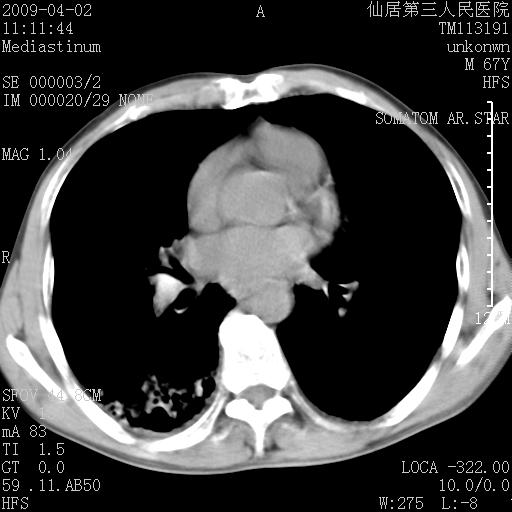

患者老年男性,乏力畏寒来诊,摄胸片示右下肺感染性病变,抗炎两周后复查胸片,无好转有进展。

后做ct平扫表现如下:

病灶呈蜂窝征,纵隔多个淋巴结肿大;肺泡癌需考虑

我认为普通的感染应该可以除外,间质性肺炎可能性较大,但如何解释纵膈的淋巴结肿大呢

考虑双肺间质性改变(间质纤维化?)伴右肺下叶感染。

考虑间质性肺炎可能性大,患者卧床吗?坠积性肺炎代排